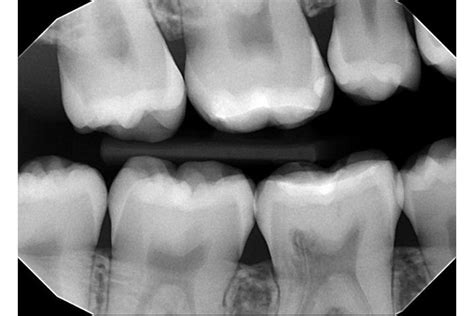

Diagnoza impaktiranega zoba se običajno začne s temeljito klinično oceno, ki jo opravi zobozdravnik. Zobozdravnik bo pregledal ustno votlino, dlesni in zobe ter ocenil prisotnost bolečine, otekline ali drugih simptomov. Ključnega pomena za natančno diagnozo so rentgenske slike. Zobni rentgen, kot je panoramski rentgen (ortopantomogram) ali posamezni rentgen (RVG), omogoča zobozdravniku, da vidi položaj, smer in morebitne zaplete impaktiranega zoba, ki niso vidni s prostim očesom. Na podlagi teh informacij lahko zobozdravnik določi najboljši načrt zdravljenja.